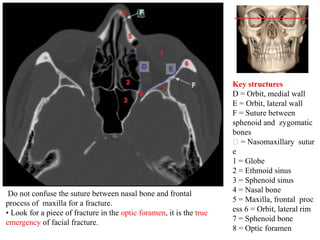

Key structures

D = Orbit, medial wall

E = Orbit, lateral wall

F = Suture between

sphenoid and zygomatic

bones

= Nasomaxillary sutur

e

1 = Globe

2 = Ethmoid sinus

3 = Sphenoid sinus

4 = Nasal bone

5 = Maxilla, frontal proc

ess 6 = Orbit, lateral rim

7 = Sphenoid bone

8 = Optic foramen

Do not confuse the suture between nasal bone and frontal

process of maxilla for a fracture.

• Look for a piece of fracture in the optic foramen, it is the true

emergency of facial fracture.